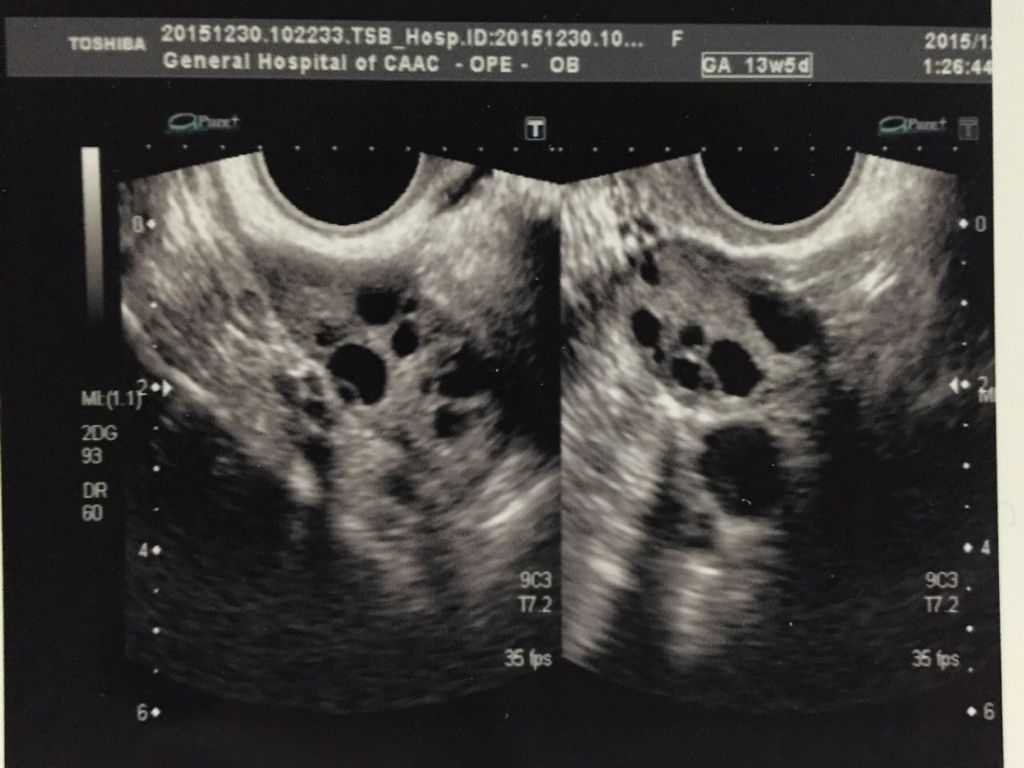

想要宝宝做了孕前检查,其中阴超报告医生说排卵少,有点多囊卵巢什么的,什么意思呢?严重吗?影响要宝宝 想要宝宝做了孕前检查,其中阴超报告医生说排卵少,有点多囊卵巢什么的,什么意思呢?严重吗?影响要宝宝吗?请高手医生给看看。谢谢。本人27周岁。 点击展开 匿名用户 2015-12-31 22:52 满意回答 从超声检查来看卵泡不够寸串圆润,是否能够成概兔吉熟排出还告搂需要后期监测才可以。没看到多囊提示。 东郭灵慧_eGp2 2015-12-31 23:00 宝宝知道提示您:回答为网友贡献,仅供参考。 为您推荐: 其他回答 就是卵子不大好 匿名用户 2015-12-31 22:56 相关问题 在丰城妇产医院孕前检查出多囊卵巢了,这个对身体有什么不好影响吗?会不会影响排卵? 我是多囊卵巢综合症,7月10号来的月经,25测的排卵同房,30号小腹疼痛了一天,请问这是怎么回事? 我是多囊卵巢综合证,孕前吃过二